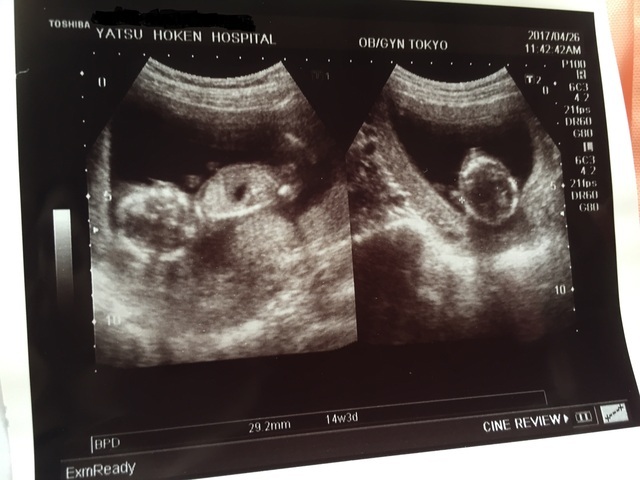

14週3日(14w3d・女の子)|ri412 さん(19歳)

エコー写真撮影時のエピソード:

健診に行きエコーをしてもらったのですがなかなかこっちに向いてくれず先生はいいエコー写真が欲しいね!とずっと角度を変えてやっとこのわかりやすい体制になってくれました!

現在8ヶ月なのですが今でもなかなか顔を見せてくれません...